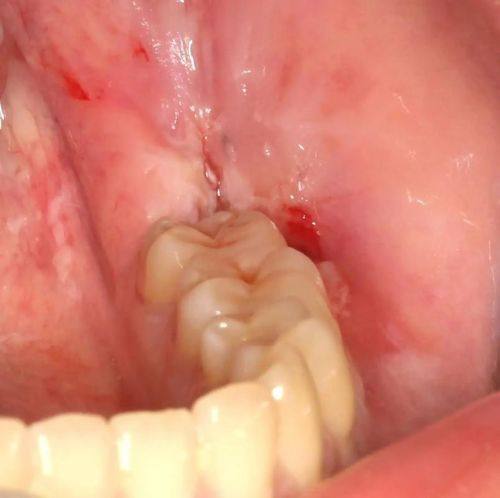

根管治疗:针对牙髓感染、根尖周病变等口腔问题,保留患牙并缓解疼痛,修复牙齿功能。

拔牙:针对阻生齿、松动牙等情况进行安心拔除,避免引发口腔健康问题。